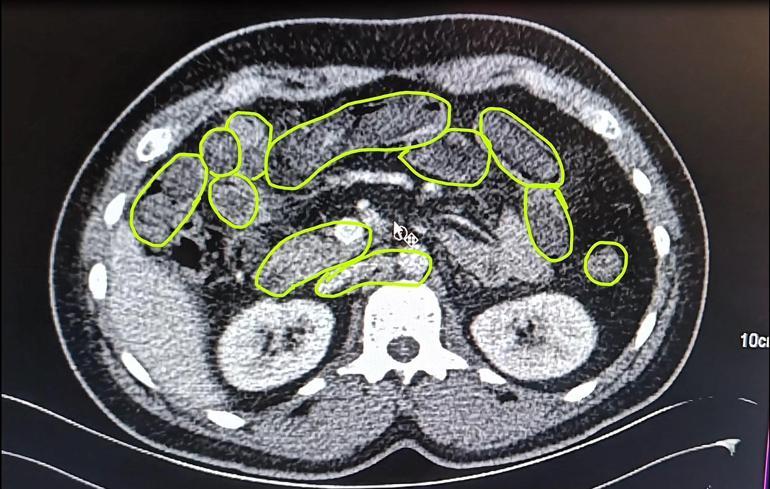

İl Jandarma Komutanlığı ekipleri, İran uyruklu A.O. (51), M.S. (37) ve P.S..'nin (28) ülkelerinden kente uyuşturucu getireceği bilgisine ulaştı. Şüpheliler Kocasinan ilçesi Himmetdede Mahallesi'nde taksi ile kente girmek istediği sırada durduruldu. Araçta yapılan aramada 15 gram esrar, 5 gram bonzai ve 117 adet uyuşturucu hap ele geçirildi. Gözaltına alınan 3 şüpheli muayene olmak üzere Kayseri Şehir Hastanesi'ne getirildi. Röntgen ve ultrason sonrası kontrollerde 3 şüphelinin midesinde uyuşturucu madde olduğu belirlendi. Şüphelilerin yuttukları uyuşturucuları kente sokmaya çalıştıkları tespit edildi. Kapsüller, sağlık ekibinin müdahalesiyle çıkarıldı. Taburcu edilen şüpheliler, İlçe Jandarma Komutanlığı'na götürüldü.